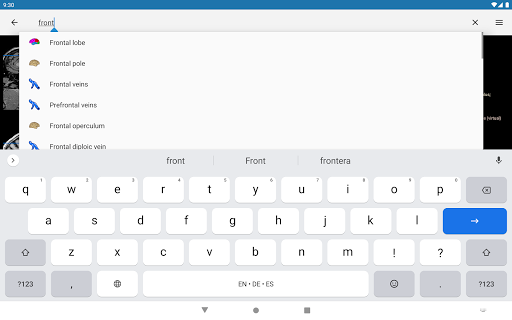

* اعثر على الأجزاء التشريحية الخاصة بك بسهولة أكبر بفضل ميزة البحث الجديدة والأكثر سهولة وقوة